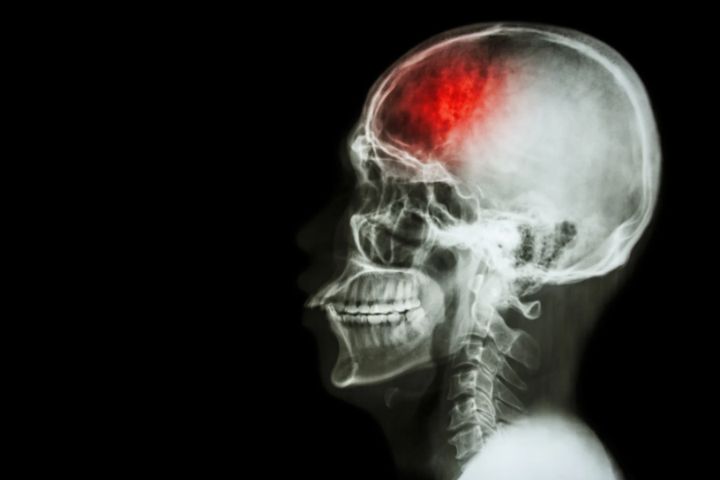

幼少期に親の離婚を経験すると「将来の脳卒中リスクが高まる」と判明

カナダ・トロント大学(University of Toronto)の研究チームは、幼少期に両親の離婚を経験した人が将来的に脳卒中を発症するリスクが高くなることを発見しました。

そして健康との相関関係を調べた結果、幼少期に両親の離婚を経験している人は、そうでない人に比べて、将来的な脳卒中の発症率が有意に高くなっていることが明らかになりました。

具体的には、他のリスク要因(糖尿病、うつ病、喫煙、運動不足、低所得など)を考慮に入れても、両親が離婚した人は脳卒中のリスクは61%高いことが示されています。